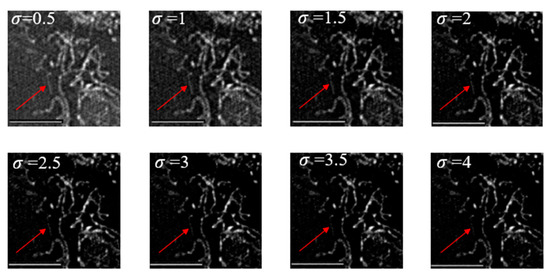

Since the principle of this method was realized by suppressing the low-frequency spectrum of the sample, it might have affected the effective information (sample structure information) of the sample. In order to verify the effectiveness of this method, an adjustable parameter was given in this paper to control the suppression of the notch function on the low-frequency of the center position. When setting different values, different results would be obtained. It can be seen from Figure 9 that the red arrow points to a mitochondrion with weak signal strength. When σ = 2, the whole image could not only suppress the background noise, but also maintain the effective information of the samples.

Figure 9. Under the 60× objective lens, when σ takes different values, N-SIM is used to reconstruct the image of mouse hepatocyte mitochondria. The length of the image scale is 5 μm.